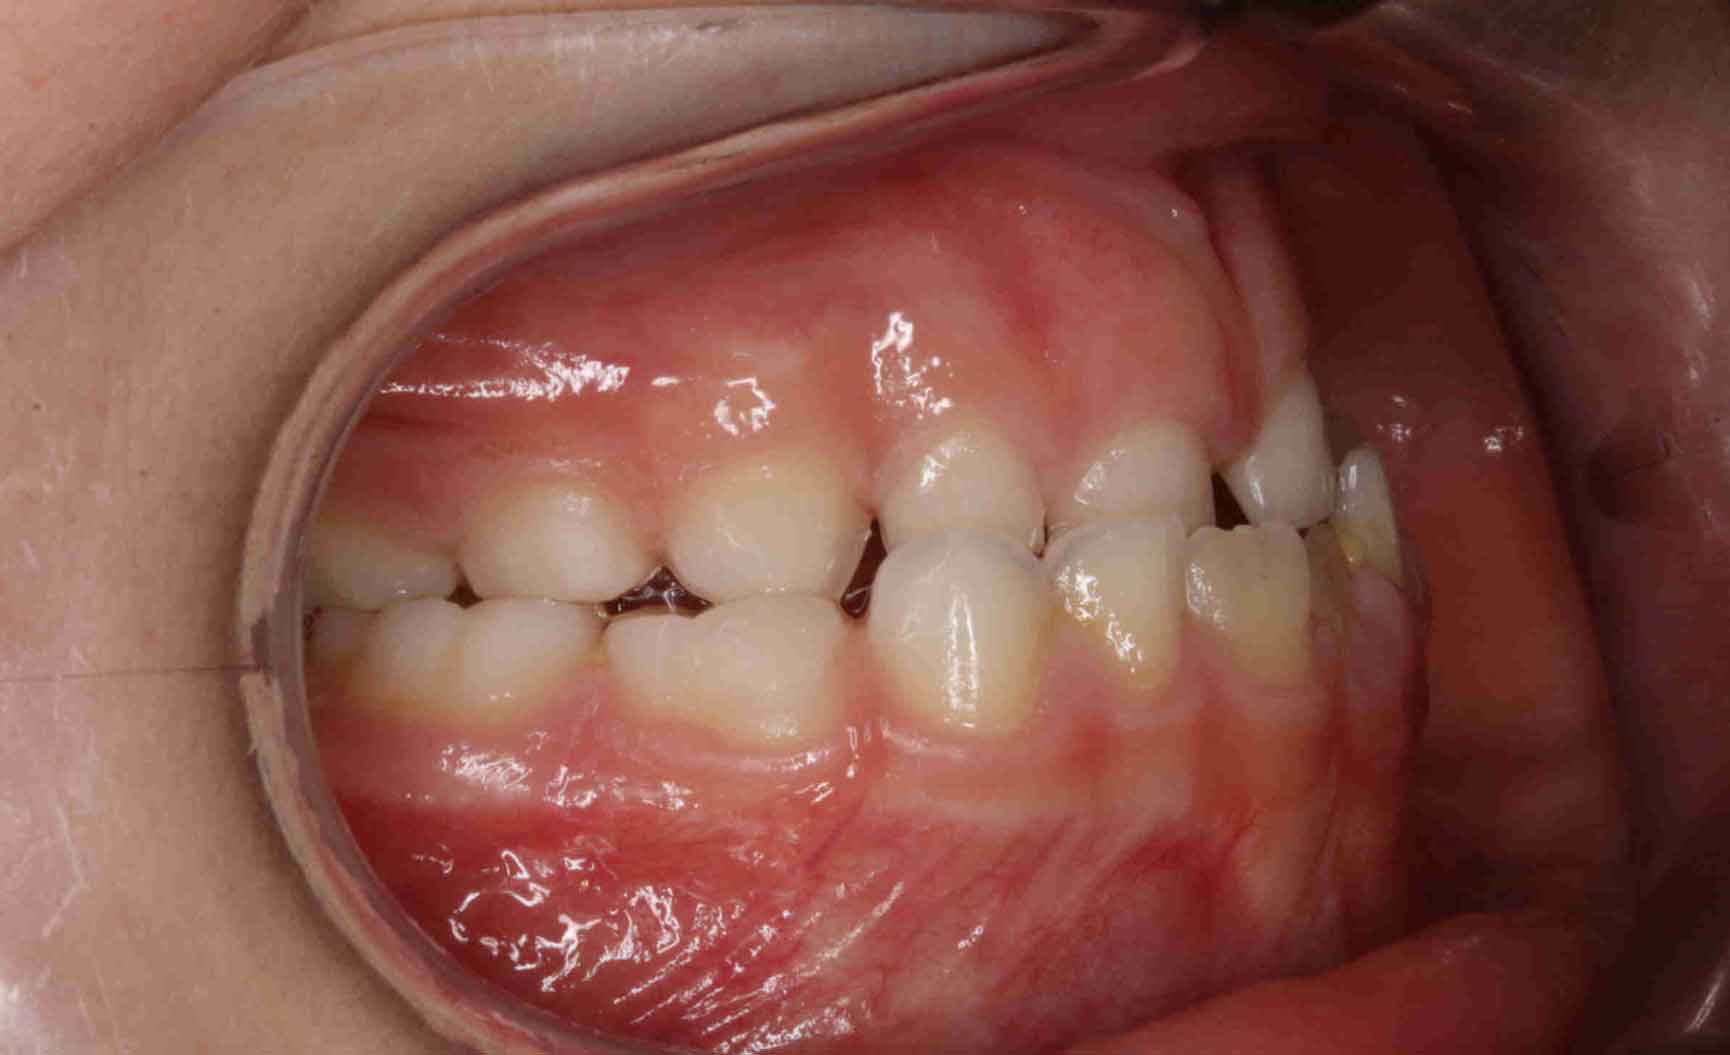

Tratamiento solo interceptivo 1ª Fase

En las siguientes imágenes puedes ver distintos resultados del tratamiento, deslizando la barra central de un lado a otro.